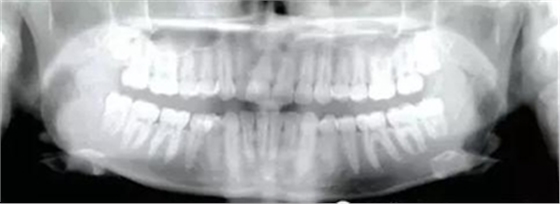

患者為19歲高加索女性,要求矯治中線不齊及上頜右側(cè)側(cè)切牙腭側(cè)異位??趦?nèi)檢查,左側(cè)安氏Ⅰ類尖牙、磨牙關(guān)系,右側(cè)安氏Ⅱ類尖牙、磨牙關(guān)系;上頜中線右偏4mm,下頜中線右偏2mm,16牙根管治療史,16及47有修復(fù)體;覆蓋5mm,覆合4mm,無橫向不調(diào)。功能檢查,顳下頜關(guān)節(jié)無明顯異常,面部及咀嚼肌不對稱。

治療目標(biāo)為:遠(yuǎn)中移動上頜右側(cè)磨牙,達(dá)到安氏Ⅰ類尖牙、磨牙關(guān)系。治療前,拔除上頜左側(cè)第三磨牙,將一直徑2mm,長14mm的鈦骨釘植入上頜腭中縫,位于切牙孔后4-5mm,中線旁3-4mm。用1.3mm直徑的鉆助攻植入螺紋釘。一周之后,取印模并灌制模型,將螺紋釘?shù)念^部用蠟包圍,從螺紋釘上延伸出連接第一前磨牙的0.8mm的鋼絲??趦?nèi)試戴后,用光固化樹脂將從螺紋釘上延伸出的弓絲與上頜第一前磨牙粘接在一起,0.016*0.022英寸不銹鋼絲片段弓加鎳鈦推簧置于上頜第一磨牙和第一前磨牙間,每側(cè)250g力推動上頜磨牙向遠(yuǎn)中,磨牙到位后拍攝頭側(cè)位片。